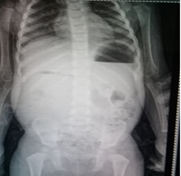

Abdominal ultrasound was normal with no hypertrophic in the pylorus. Barium enema was normal that exclude Hirschsprung disease. Abdominal X-ray showed expansion in the stomach with malposition of gases (Figure 1). Esophagogastroduodenoscopy (EGD) was performed that showed severe duodenal expansion at segment 2 followed by severe narrowing and inability to cross. An abdominal computed tomography scan (CT) showed the annular pancreas surrounding segment 2 of the duodenum (Figure 2). The patient did not have associated anomalies of the annular pancreas (Echocardiography, ECG, and abdominal ultrasound did not show any anomaly). The patient underwent surgery, an incomplete annular pancreas with duodenal stenosis in the second portion of the duodenum was observed. Duodenojejunostomy was performed (Figure 3a, 3b). The postoperative course was uncomplicated, and oral feeding was tolerated from the fourth day. The patient was discharged from the hospital on the 8th day after the operation. On follow-up, the patient was asymptomatic with normalweightgain.

Figure 1 Abdominal X-ray showed expansion in the stomach with malposition of gases.